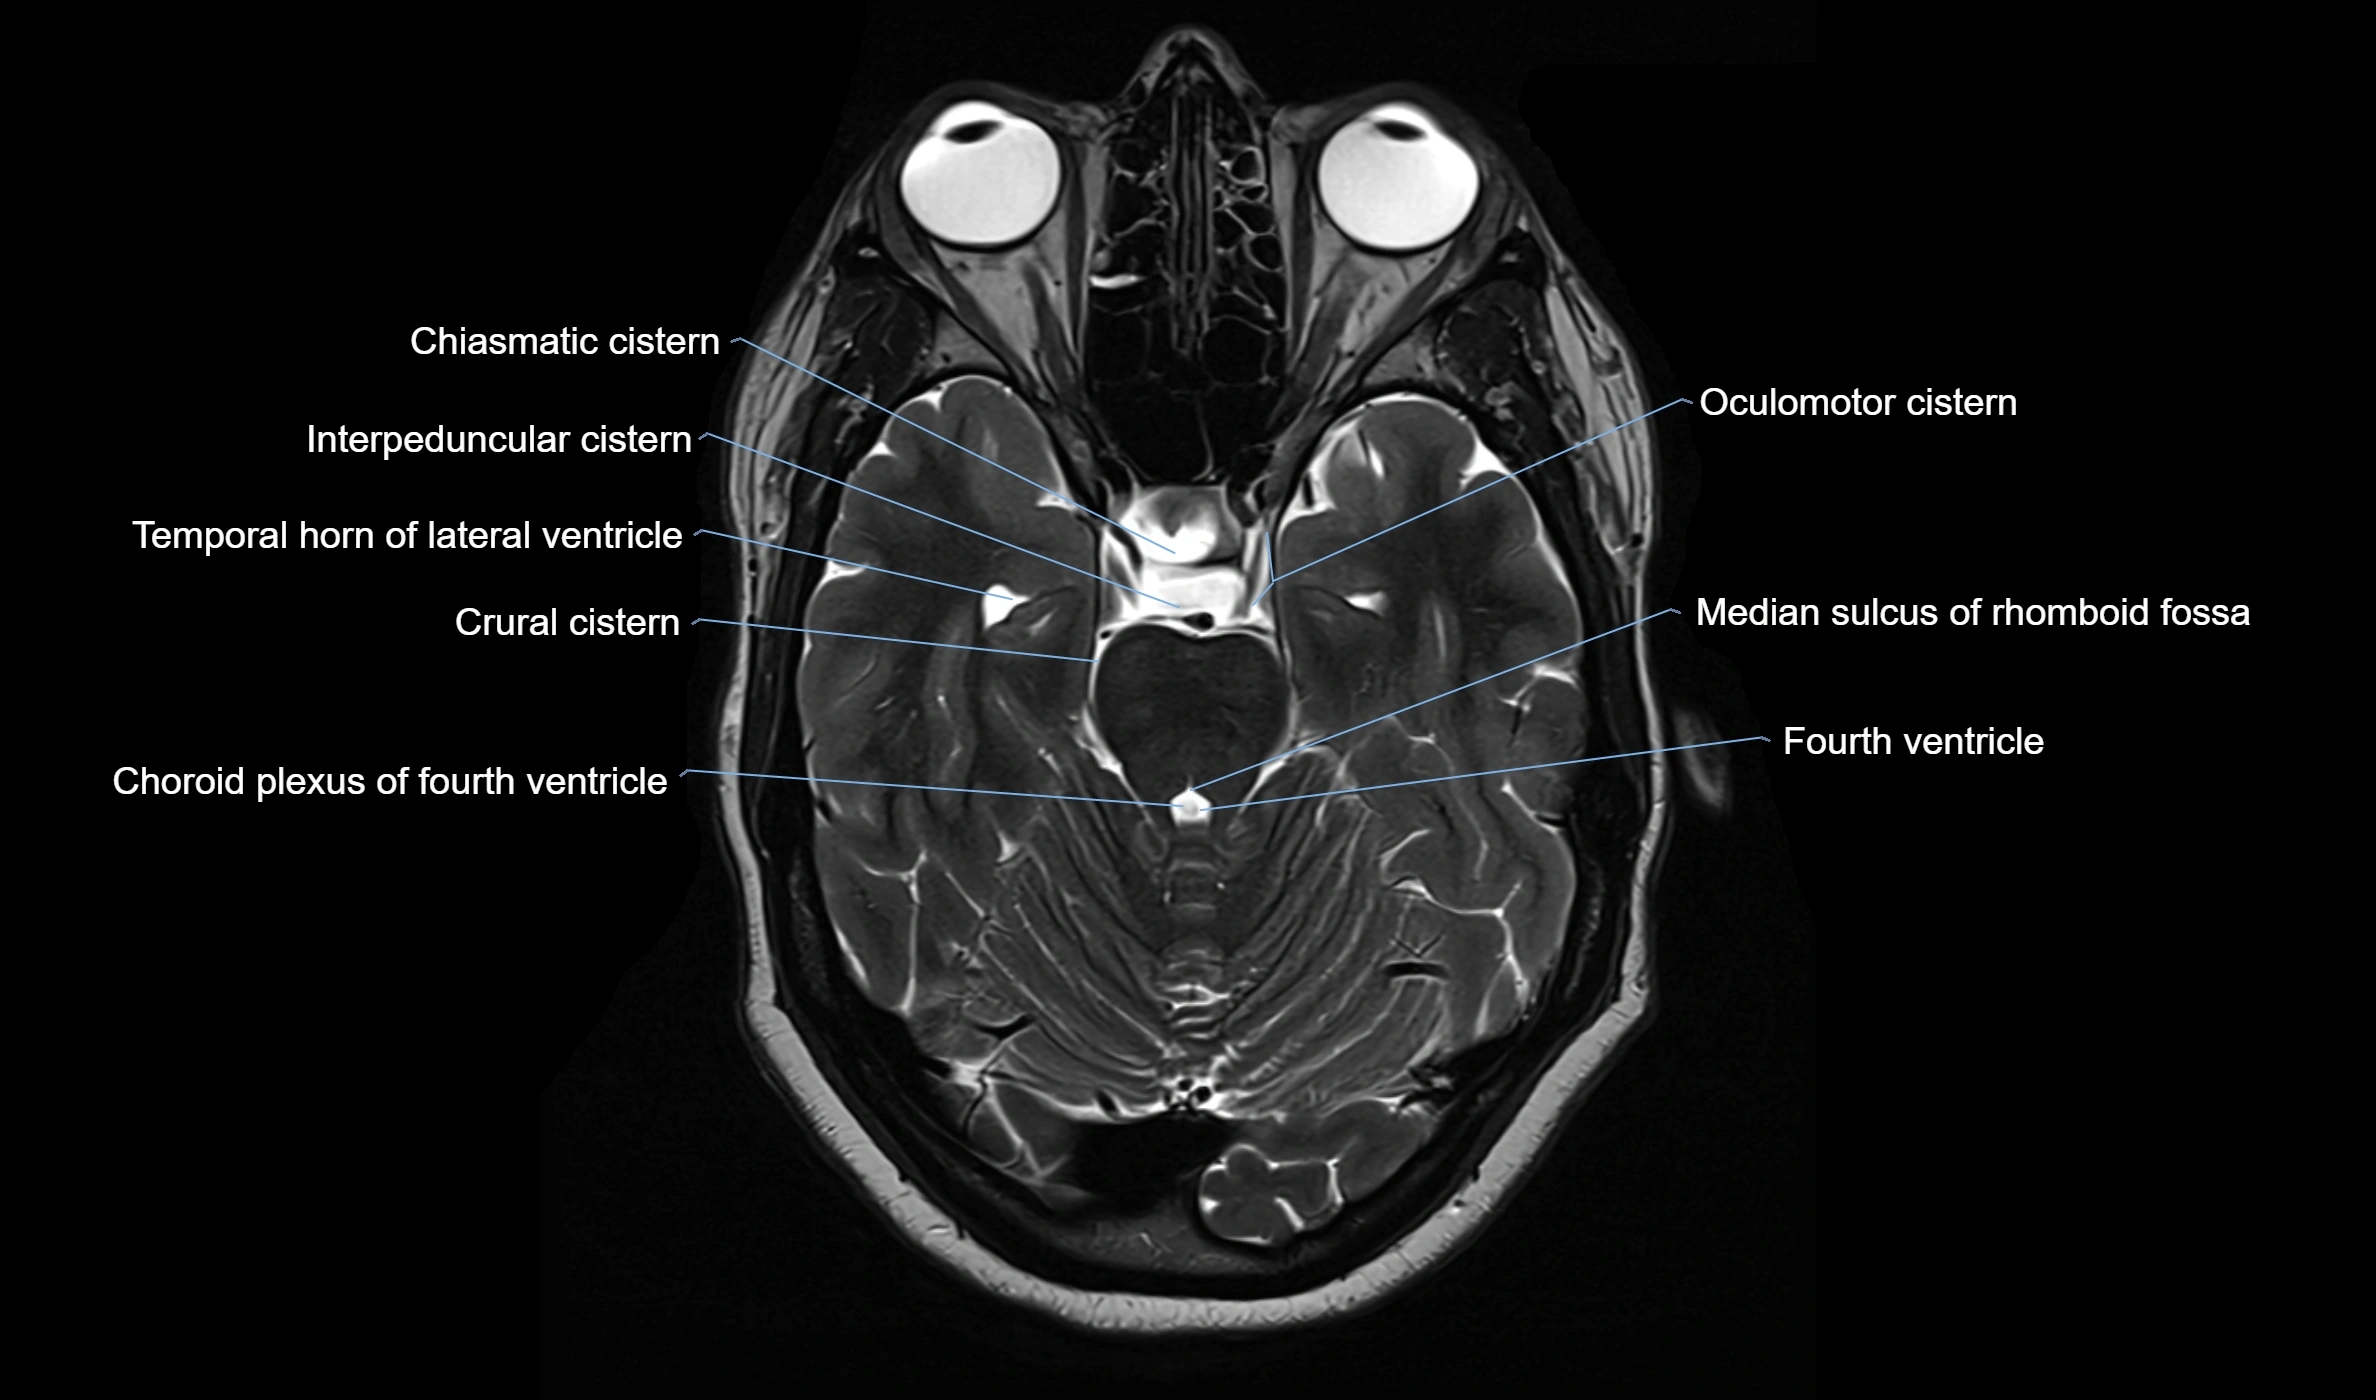

MRI images

image